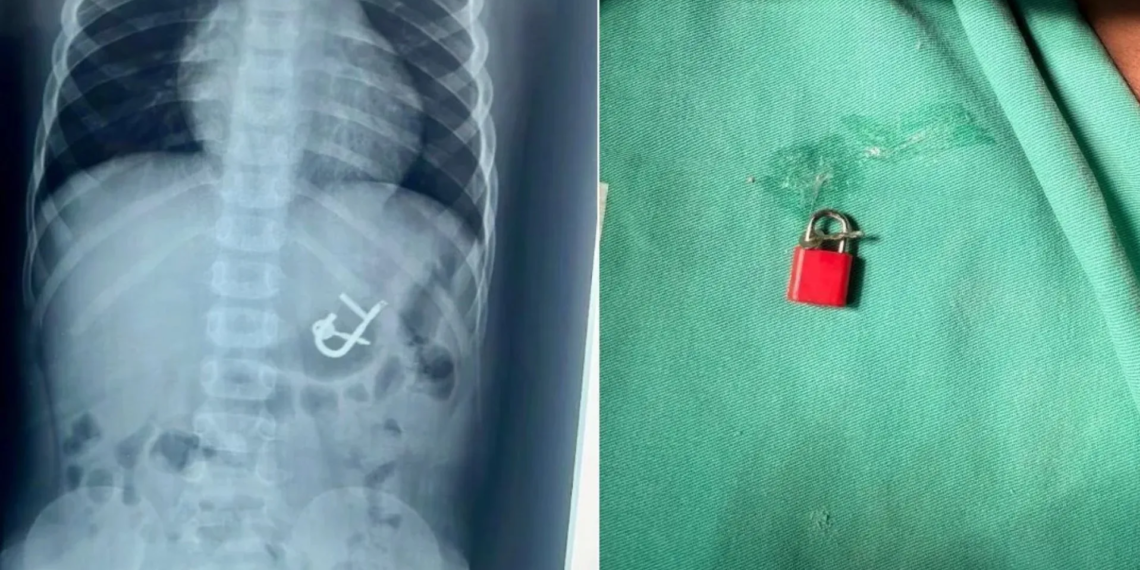

Uma criança de quatro anos passou por uma endoscopia digestiva para a remoção de um cadeado com as chaves no Hospital Regional Inácio de Sá, em Salgueiro, no Sertão de Pernambuco, após engolir o objeto durante uma brincadeira. O procedimento, realizado com sucesso na última sexta-feira (10), permitiu que o menino recebesse alta médica no mesmo dia.

Em entrevista à CNN nesta quarta-feira (15), a diretora médica Thaís Sampaio explicou como realizou o procedimento no garoto, que, tentando retirar as chaves do cadeado, perdeu o equilíbrio e acabou caindo e engolindo o objeto, de aproximadamente 5 cm.

“A retirada foi tranquila. Assim que entramos, já avistamos o cadeado no estômago, como mostrava o Raio-x. Usamos uma pinça especializada e uma cestinha, que chamamos de basket. Você tem uma pinça especializada para isso. E conseguimos retirar por via oral, sem nenhuma lesão. Não houve danos no estômago nem no esôfago, e todo o procedimento transcorreu na maior tranquilidade”, explicou a doutora Thaís Sampaio.